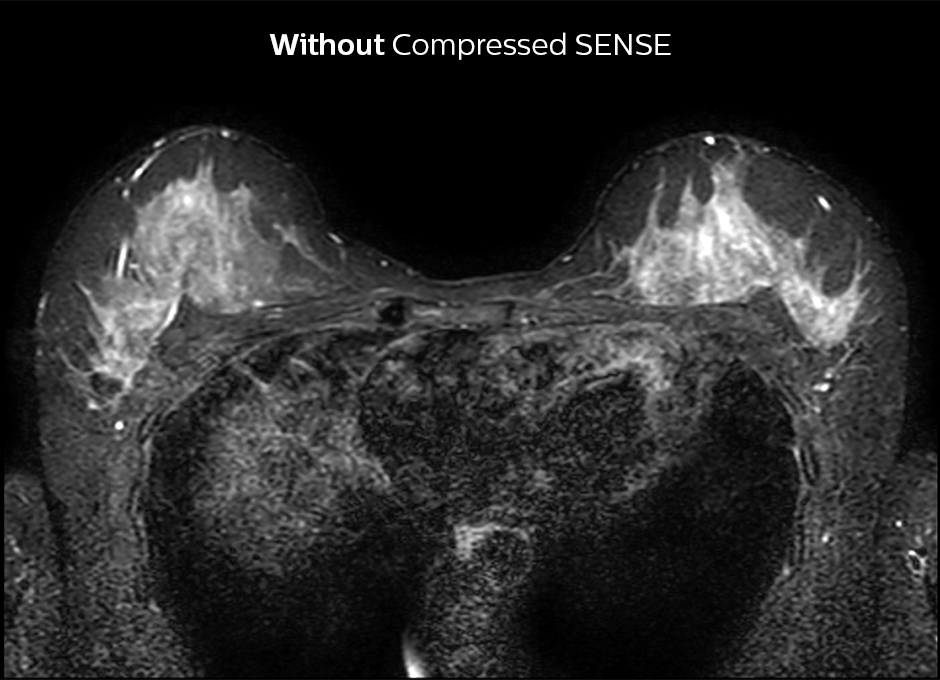

In het KSW-ziekenhuis wordt Compressed SENSE ook toegepast om de scantijd bij een MRI onderzoek van de borsten te verkorten. 2D STIR is nu sneller en sequenties die silicone zichtbaar maken zijn bijvoorbeeld 30% sneller. De post-contrast 3D T1 THRIVE kan met ongeveer 40% worden versneld en Compressed SENSE wordt momenteel toegevoegd aan de dynamische T1-sequentie om een hogere resolutie te krijgen in dezelfde scantijd.

Compressed SENSE verkort de scantijd met 29%, mét behoud van een gelijkaardige ruimtelijke resolutie.

2D STIR, scantijd 3:39 min, voxelgrootte 1x1,25x3 mm.

2D STIR, scantijd 2:36 min, voxelgrootte 1x1,26x3 mm.